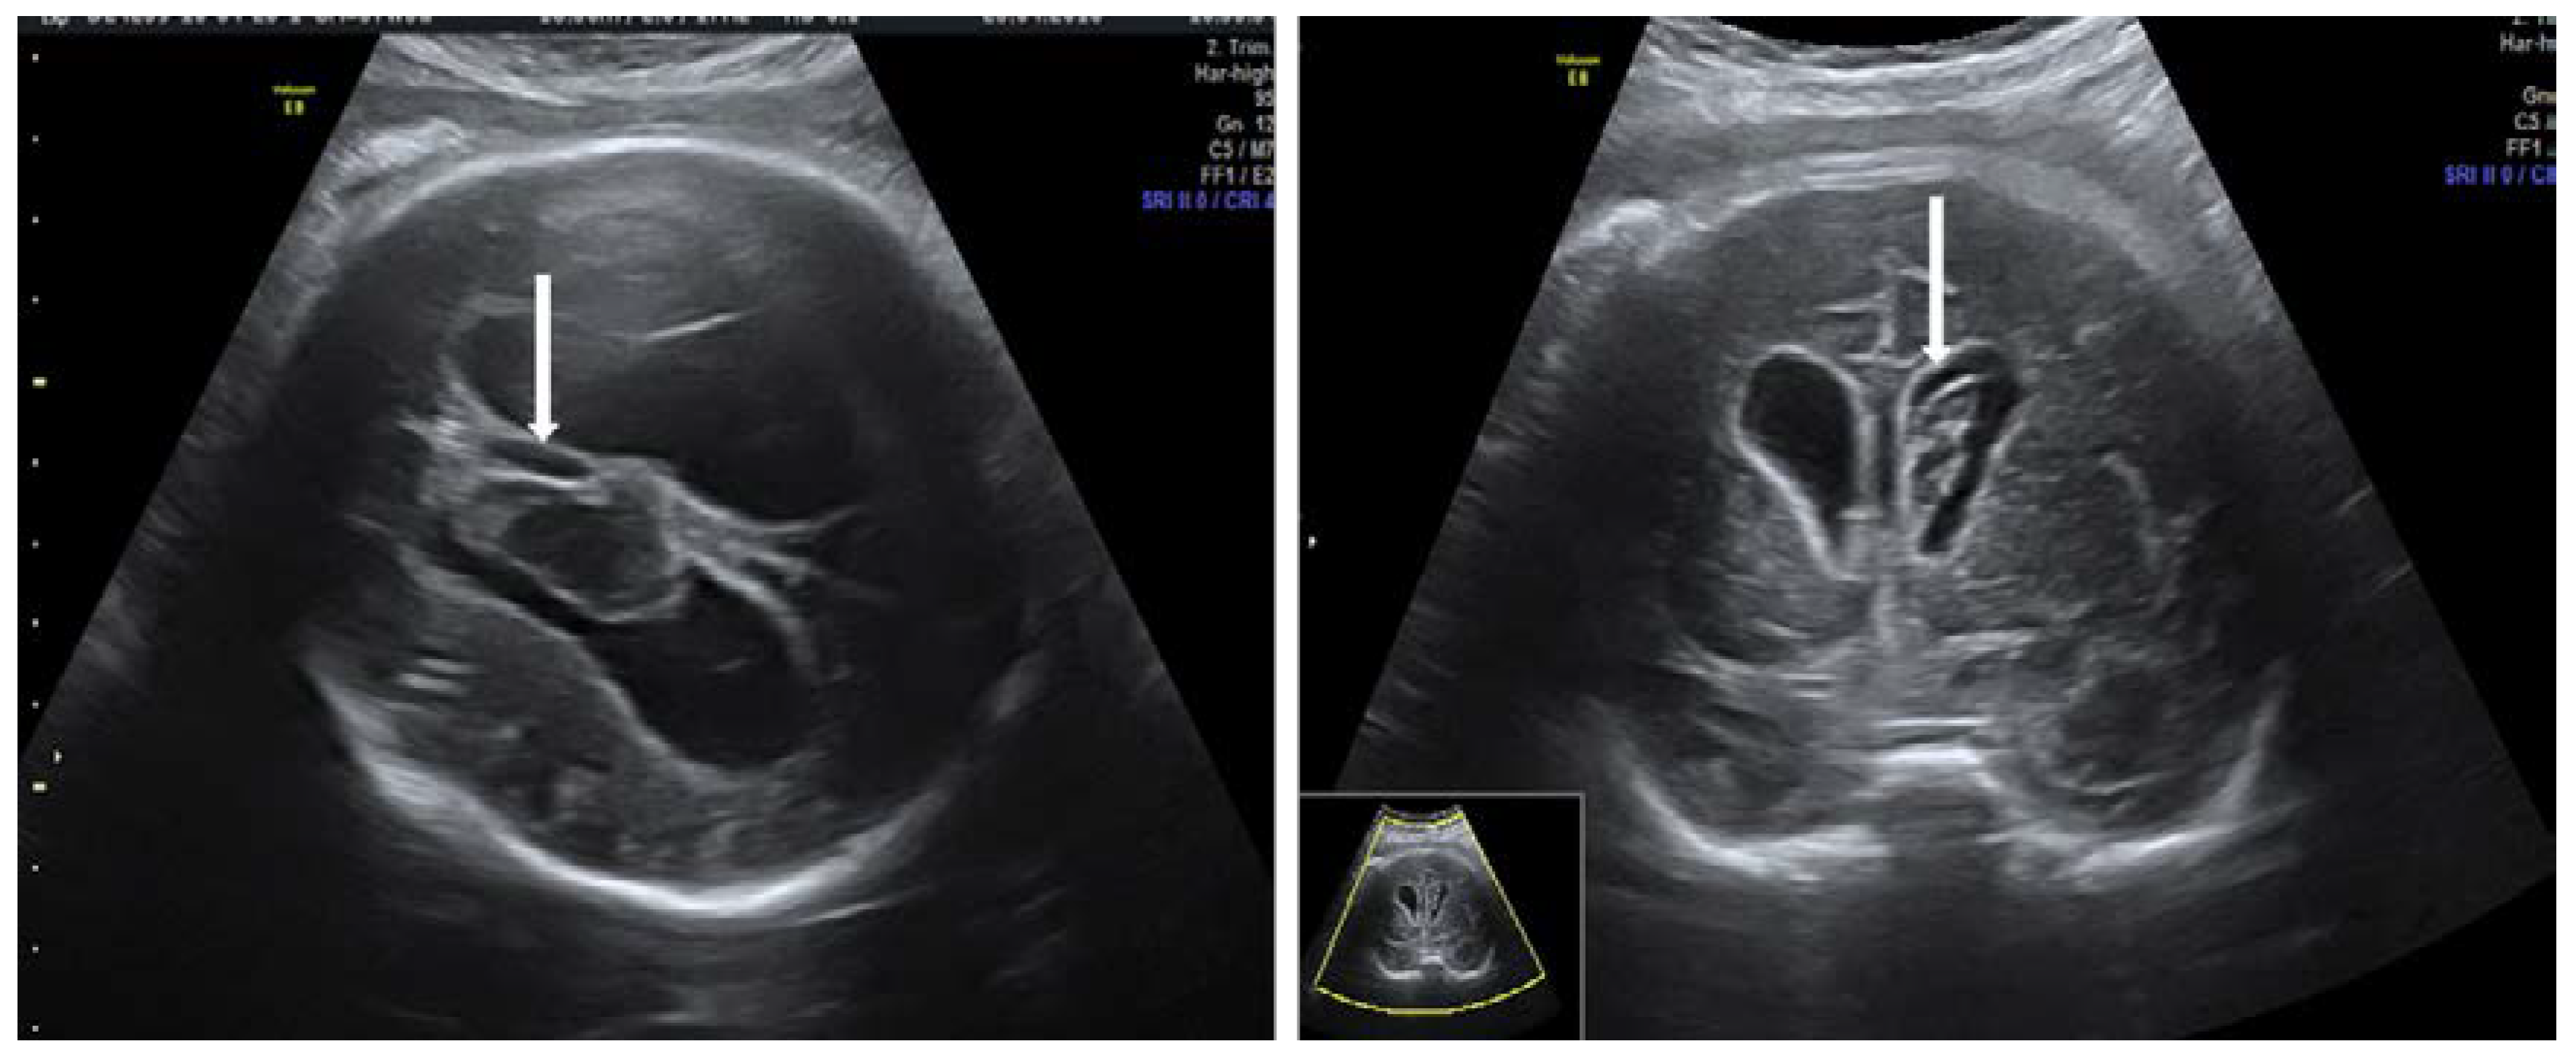

- Huel, C.; Guibourdenche, J.; Vuillard, E.; Ouahba, J.; Piketty, M.; Oury, J.F.; Luton, D. Use of ultrasound to distinguish between fetal hyperthyroidism and hypothyroidism on discovery of a goiter. Ultrasound Obstet. Gynecol. 2009, 33, 412–420. [Google Scholar] [CrossRef] [PubMed]

- Panaitescu, A.; Nicolaides, K. Fetal Goitre in Maternal Graves’ Disease. Acta Endocrinol. (Buchar.) 2018, 14, 85–89. [Google Scholar] [CrossRef]

- Eliasson, H.; Sonesson, S.E.; Sharland, G.; Granath, F.; Simpson, J.M.; Carvalho, J.S.; Jicinska, H.; Tomek, V.; Dangel, J.; Zielinsky, P.; et al. Isolated atrioventricular block in the fetus: A retrospective, multinational, multicenter study of 175 patients. Circulation 2011, 124, 1919–1926. [Google Scholar] [CrossRef]

- Donofrio, M.T.; Moon-Grady, A.J.; Hornberger, L.K.; Copel, J.A.; Sklansky, M.S.; Abuhamad, A.; Cuneo, B.F.; Huhta, J.C.; Jonas, R.A.; Krishnan, A.; et al. Diagnosis and Treatment of Fetal Cardiac Disease: A Scientific Statement from the American Heart Association. Circulation 2014, 129, 2183–2242. [Google Scholar] [CrossRef]